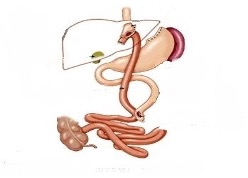

Γαστρική παράκαμψη (gastric bypass)

Το γαστρικό bypass είναι, με τα σημερινά διεθνή δεδομένα, η επικρατούσα χειρουργική επέμβαση για την κακοήθη παχυσαρκία (BMI > 50) και έχει αποδείξει την αποτελεσματικότητα αλλά και την ασφάλειά του σε σχέση με τις άλλες βαριατρικές επεμβάσεις, αποτελώντας το gold standard.

Από το 1994 γίνεται λαπαροσκοπικά και την τελευταία 10ετία πραγματοποιείται ρομποτικά. Το στομάχι χωρίζεται και δημιουργείται ένας νέος μικρότερος θάλαμος στον οποίο συνδέεται μέρος του λεπτού εντέρου.

Η νέα ανατομία του πεπτικού που δημιουργείται έτσι οδηγεί σε:

α) Περιορισμό του όγκου του στομάχου, με αποτέλεσμα τη μείωση της ποσότητας φαγητού που μπορεί να δεχτεί.

β) Μείωση των απορροφούμενων τροφών/θερμίδων (δυσαπορρόφηση)

γ) Ορμονικές μεταβολές στο λεπτό έντερο, που συμβάλλουν στην απώλεια θερμίδων.

Η επιστροφή στην εργασία είναι άμεση και ο ασθενής πρέπει να γνωρίζει ότι είναι πολύ πιθανό να χρειαστεί να λαμβάνει υποκατάστατα κάποιων βιταμινών και ιχνοστοιχείων που δεν θα απορροφώνται ικανοποιητικά. Αυτό, δυστυχώς, αποτελεί μείζον μειονέκτημα της μεθόδου καθώς απαιτείται συνεχής παρακολούθηση από ενδοκρινολόγο.

Γαστρική παράκαμψη (gastric bypass)

Το γαστρικό bypass είναι, με τα σημερινά διεθνή δεδομένα, η επικρατούσα χειρουργική επέμβαση για την κακοήθη παχυσαρκία (BMI > 50) και έχει αποδείξει την αποτελεσματικότητα αλλά και την ασφάλειά του σε σχέση με τις άλλες βαριατρικές επεμβάσεις, αποτελώντας το gold standard.

Από το 1994 γίνεται λαπαροσκοπικά και την τελευταία 10ετία πραγματοποιείται ρομποτικά. Το στομάχι χωρίζεται και δημιουργείται ένας νέος μικρότερος θάλαμος στον οποίο συνδέεται μέρος του λεπτού εντέρου.

Η νέα ανατομία του πεπτικού που δημιουργείται έτσι οδηγεί σε:

α) Περιορισμό του όγκου του στομάχου, με αποτέλεσμα τη μείωση της ποσότητας φαγητού που μπορεί να δεχτεί.

β) Μείωση των απορροφούμενων τροφών/θερμίδων (δυσαπορρόφηση)

γ) Ορμονικές μεταβολές στο λεπτό έντερο, που συμβάλλουν στην απώλεια θερμίδων.

Η επιστροφή στην εργασία είναι άμεση και ο ασθενής πρέπει να γνωρίζει ότι είναι πολύ πιθανό να χρειαστεί να λαμβάνει υποκατάστατα κάποιων βιταμινών και ιχνοστοιχείων που δεν θα απορροφώνται ικανοποιητικά. Αυτό, δυστυχώς, αποτελεί μείζον μειονέκτημα της μεθόδου καθώς απαιτείται συνεχής παρακολούθηση από ενδοκρινολόγο.